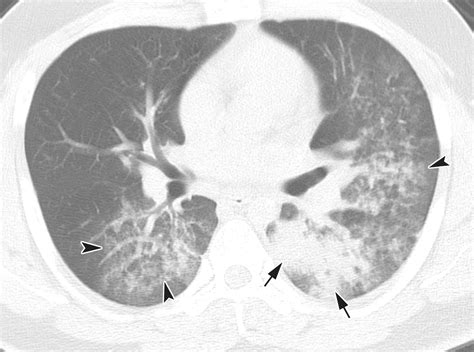

Once the scan is completed, a radiologist will interpret the images and generate a report. When viewing a Pneumonia CT Scan, medical professionals look for specific patterns of lung involvement. These patterns often indicate the type of pneumonia or the severity of the inflammatory response.

Common findings often described in reports include:

• Consolidation: This refers to the filling of air spaces (alveoli) with fluid, pus, or other material, appearing as dense, white areas on the scan.

• Ground-Glass Opacity (GGO): A hazy appearance in the lungs, indicating partial filling of air spaces or thickening of the lung interstitium. This is often seen in viral pneumonias.

• Bronchograms: The appearance of air-filled bronchi surrounded by consolidated lung tissue.

• Pleural Effusion: The buildup of fluid in the space between the lung and the chest wall.

• Nodules or Cavitation: These findings may prompt further investigation to rule out other infections or malignancy.

It is important to remember that these findings must always be correlated with the patient's symptoms, laboratory results, and clinical history. A report with "positive findings" does not always imply a worst-case scenario, as many patterns are typical of common bacterial or viral infections.